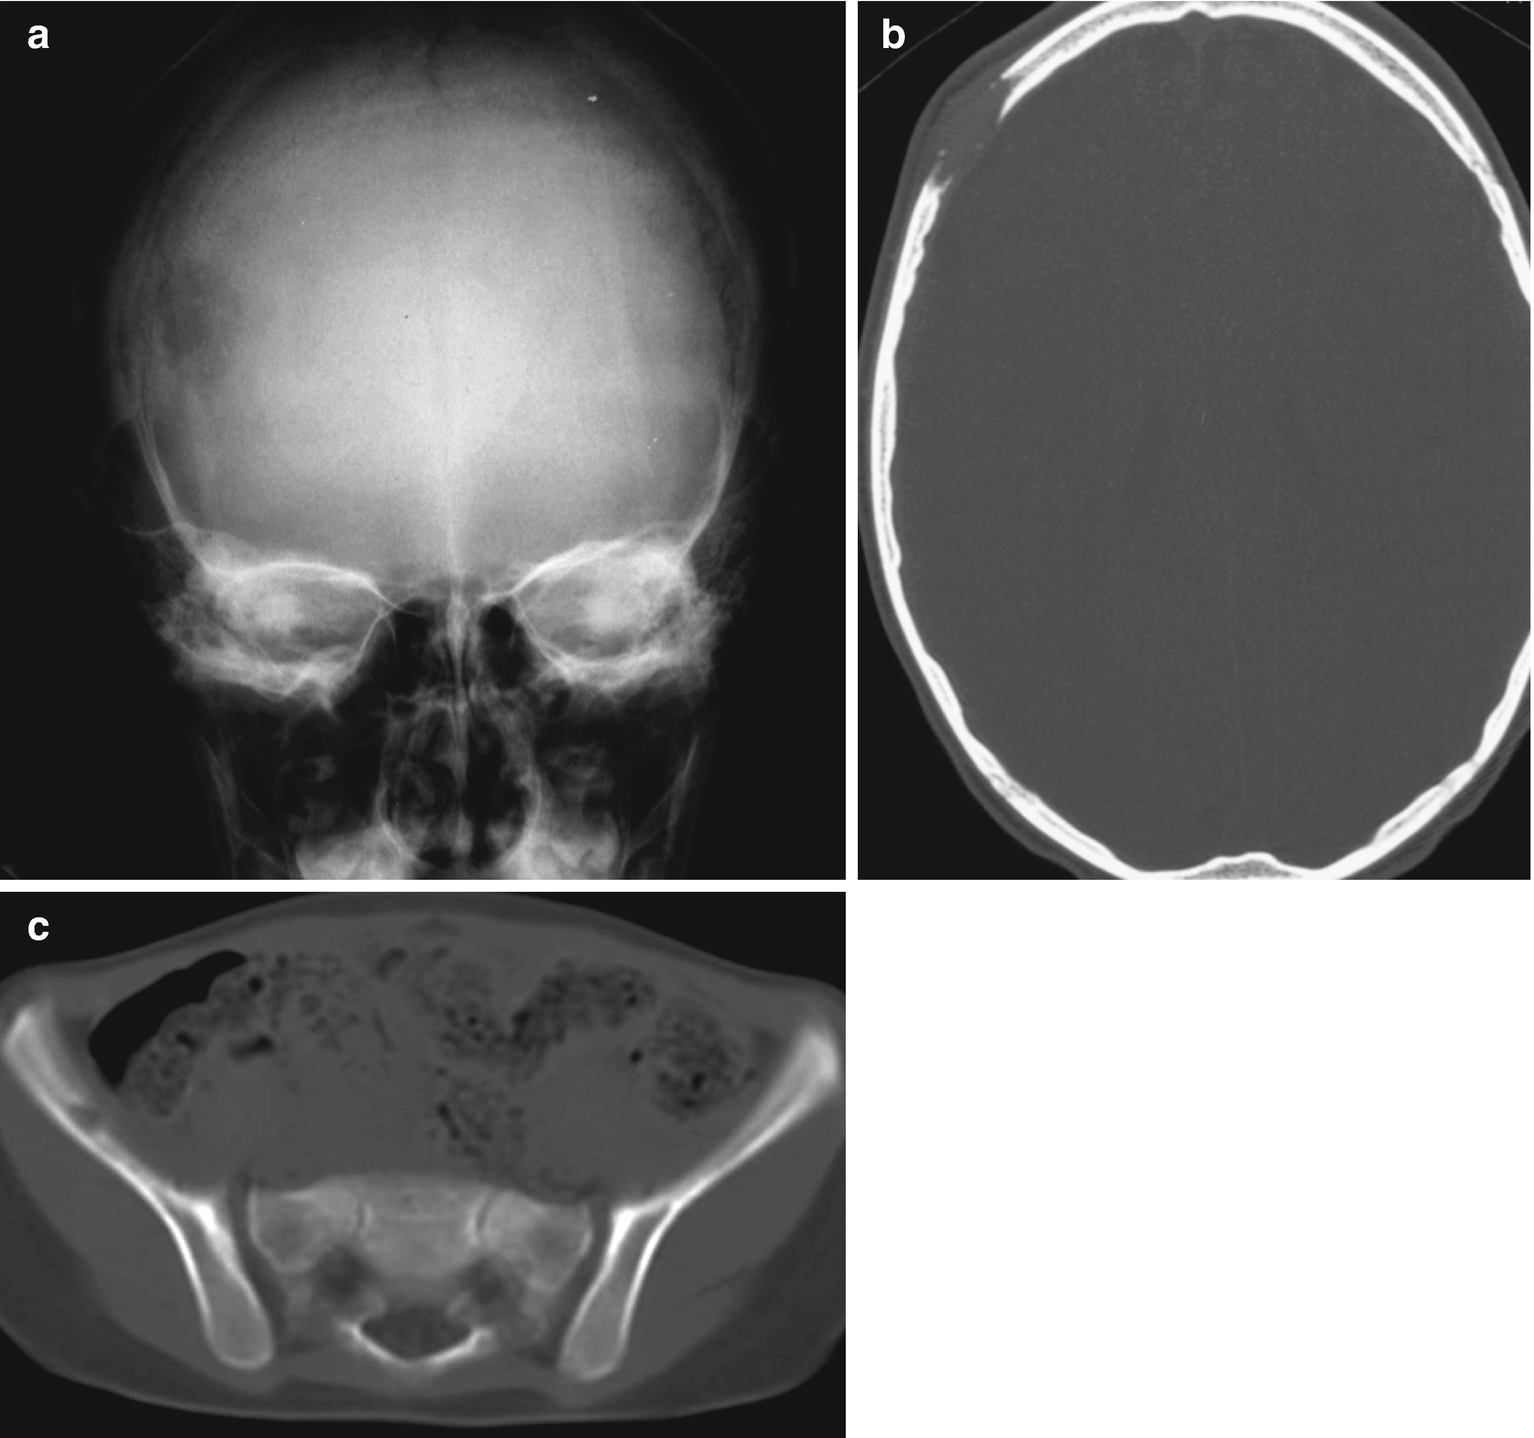

Chronic disseminated langerhans cell disease. Hand-Schuller-Christian disease is characterized by widespread skeletal and extra skeletal lesions and a chronic clinical course. The clinical presentation of Langerhans cell histiocytosis LCH depends on the extent of dissemination. Moghadam et al 1991.

Langerhans cell histiocytosis LCH previously known as histiocytosis X is a rare disease of unknown ethiology characterized by intense and abnormal proliferation of bone marrow-derived histiocytes Langerhans cells. Langerhans cells which help regulate the immune system are normally found throughout the body especially in the skin lymph nodes spleen lungs liver and bone marrow. Chronic disseminated Langerhans cell disease A.

RENZETTI AD Jr EASTMAN G AUCHINCLOSS JH Jr. Produces bony defects as focal areas of bony rarefaction. It can present both local and systemic manifestations involving bone skin and mucosal tissues and internal organs.

It occurs usually before the age of five but has been reported even in young adults. Langerhans cell histiocytosis LCH is a disorder that primarily affects children but is also found in adults of all ages. 13410973 PubMed - indexed for MEDLINE MeSH Terms.

Pdf Oral Manifestations Of Chronic Disseminated Langerhans Cell Histiocytosis A Case Report Semantic Scholar

Langerhans cell histiocytosis a chronic disseminated forms ie. The clinical presentation of Langerhans cell histiocytosis LCH depends on the extent of dissemination. The clinical spectrum includes on one end an acute fulminant disseminated disease called Letterer-Siwe disease and on the other end solitary or few indolent chronic lesions of bone and other organs called Eosinophilic granuloma. It occurs usually before the age of five but has been reported even in young adults. Langerhans cell histiocytosis LCH is a disorder that primarily affects children but is also found in adults of all ages. Produces a solitary eosinophilic lesion. Langerhans cell histiocytosis describes a disorder of the reticuloendothelial system which is characterized by an abnormal proliferation of histiocytes and eosinophilic leukocytes Watanabe 1990.